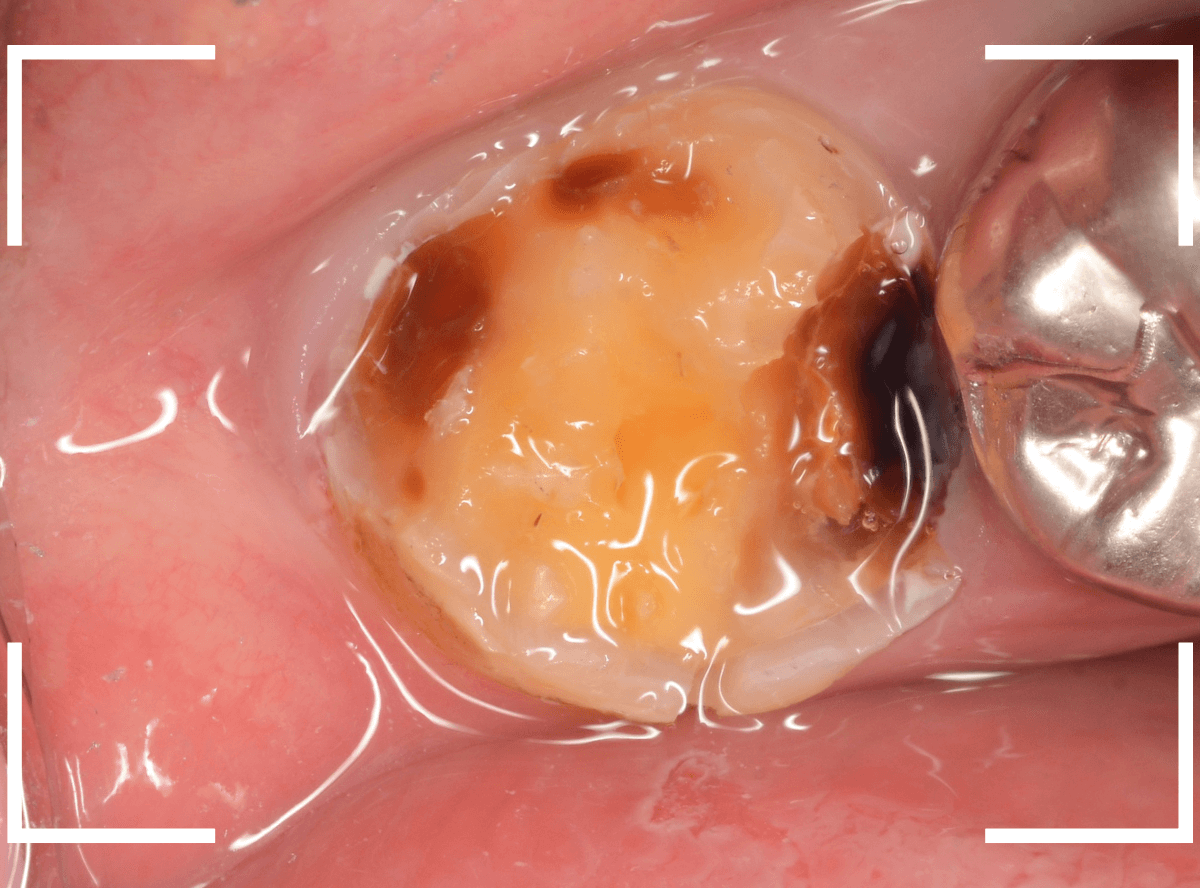

Case.11 外れたつめものの中は、ひどい虫歯

「上の奥歯のつめものが外れた」という訴えで来院された患者さんの例です。

つめものの外れてしまったつめものの中が虫歯になっているのが見えます。

レントゲン写真で確認します。

赤いラインが虫歯、青いラインが歯の神経です。

現在、つめてあるレジンの中まで虫歯が大きく進行し、ほぼ神経まで達しているのがわかります。

虫歯の治療を開始します。

奥につめてあるレジンも除去して中を確認します。

さらに慎重に虫歯を除去します。

手前の歯まで虫歯が進行しているのがわかります。

全ての虫歯を除去したところです。

薄皮一枚、神経ギリギリのところで虫歯を食い止められました。

しばらくは、お薬をつめて経過観察が必要です。

今回、つめものが外れてしまったのは、つめものの中が虫歯になったせいだと考えられます。

今回は、つめものが外れたのが受診のきっかけになったのが不幸中の幸いでした。